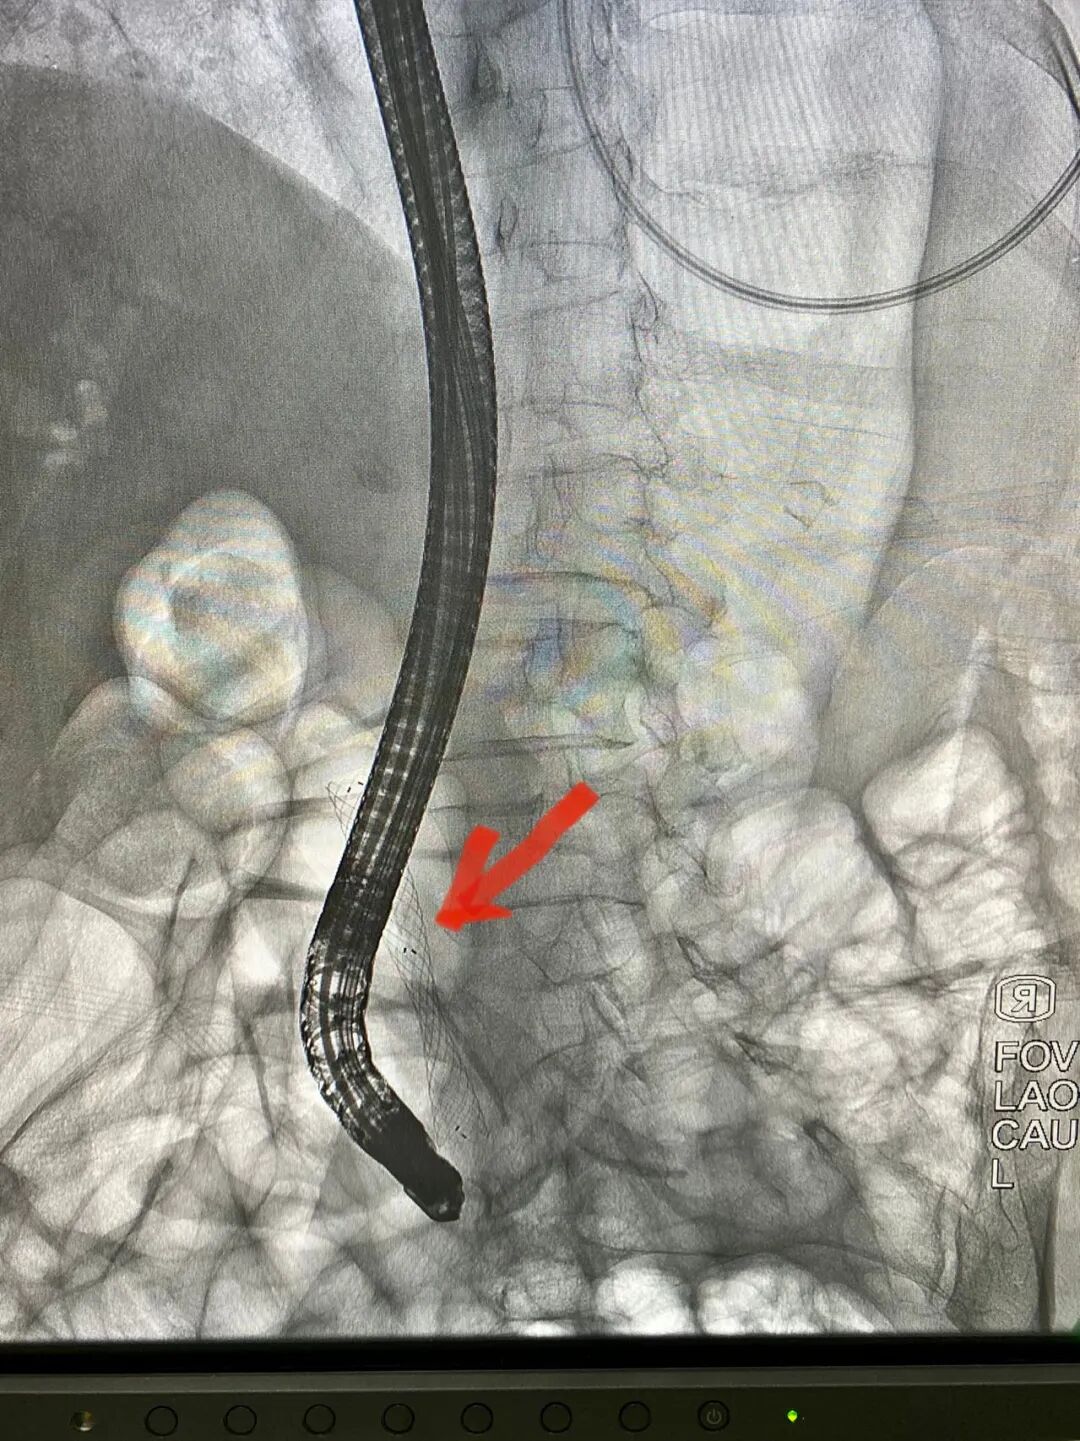

直视下精准活检

胆什么导管一目了然!胆胰成像导管操作技术——让胆胰管疾病无处遁形!_https://www.jmylbn.com_新闻资讯_第6张

术后成功放置胆道支架

术中,卢王主任使用十二指肠镜顺利插入十二指肠乳头,造影显示胆总管近十二指肠入口处狭窄,为进一步明确狭窄性质,进行了一次性使用电子胰胆管内窥镜直视下的胆道探查。在一次性胆道镜直视下可见胆总管下段新生物形成,表面凹凸不平,充血粗糙,局部狭窄形成,直视下精准活检成功明确诊断,并放置了胆道金属支架。整台手术仅耗时约30分钟,顺利完成。术后王奶奶黄疸逐渐减轻,食欲增加,恢复正常生活。